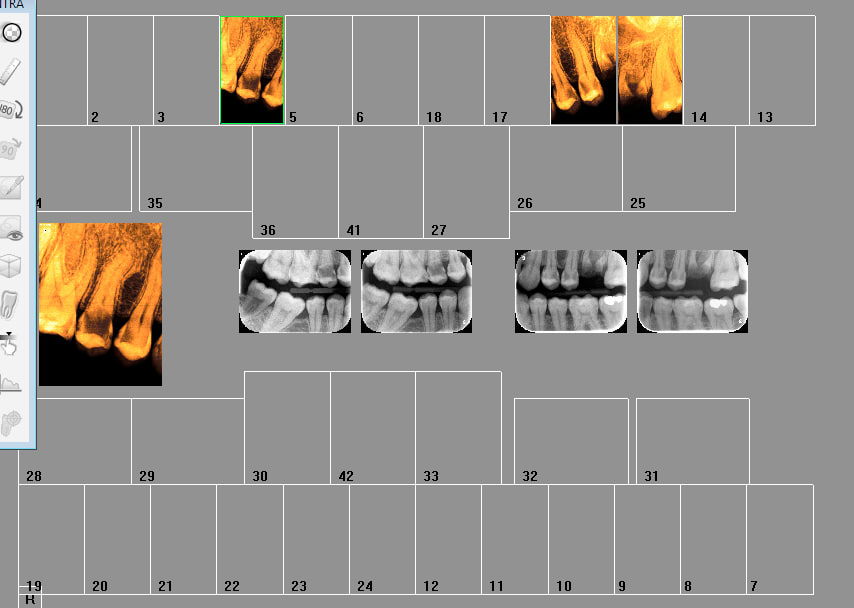

Hors signe d'appel ( ou un panoramique peut etre réalisé) la conduite à tenir c'est

1. rétrocoronaires.

2. rétro alvéolaires en cas de caries pénétrantes, reconstitutions larges ou profondes, tt endo antérieur et dents blettes. -)

Combien de secteurs ici ?